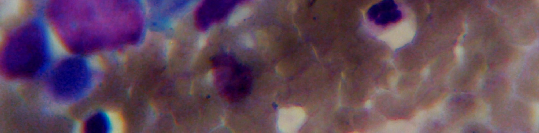

Рисунок 1 - Влагалищный мазок.

Плоскоклеточный ороговевающий рак шейки матки.

Окраска по Папенгейму, 400